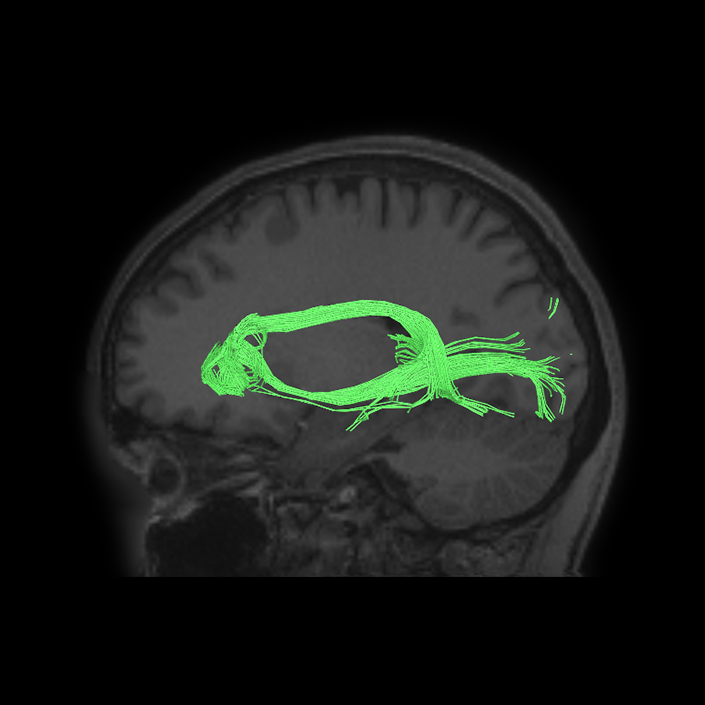

ᐅ SummaryArea 44: part of the inferior frontal gyrus of the lateral frontal lobe. Translates abstract and intentional information in the prefrontal cortex to more detailed representations to help guide the production of verbal and manual actions. In addition to its known association with Broca's area, is sometimes represented as part of Broca's complex ᐅ Where is it?Area 44 is at the posterior most part of the inferior frontal gyrus. It is the anterior bank of pars opercularis of the IFG. ᐅ What are its borders?Area 44 borders area 45 anteriorly and area 6r posteriorly. Area 8C is its medial border and its inferior border is wedged between then upper borders of Areas 6R and 6V. Its superior edge borders IFSp and IFJa. Its opercular surface is FOP4. ᐅ What are its functional connections?Area 44 demonstrates functional connectivity to areas SFL, IFSp, IFJa, 45, 47s, 47L, 9a, 9m, 8AV, 8BL and 8C in the dorsolateral frontal lobe, area 8BM in the medial frontal lobe, area 55b in the premotor areas, areas FOP5, AVI and PSL in the insula- opercular region, areas TGd, STSdp and STSvp in the temporal lobe, areas PFm, and PGi in the inferior parietal lobe, and no areas in the medial parietal lobe. ᐅ What are its white matter connections?Area 44 is structurally connected to the arcuate/SLF and the FAT. Connections with the arcuate/SLF project posteriorly and wrap around the Sylvian fissure to the middle temporal gyrus to end at TE1a and TE1m. There are also projections from the arcuate/SLF before it terminates to parcellations A5 and STSdp. The majority of the inferior connections of the frontal aslant tract end at 44, the tract is connected superiorly to superior frontal gyrus parcellations SFL, 6ma and s6-8. Local short association bundles are connected with 45 and 8C. White matter tracts from 44 in the right hemisphere have less consistent connections with the arcuate/SLF. ᐅ What is known about its function?Area 44 translates abstract and intentional information in the prefrontal cortex to more detailed representations to help guide the production of verbal and manual actions. Area 44, in addition to its known association with Broca's area, is sometimes represented as part of "Broca's complex", including Brodmann Areas 45, 46, 47 and the mesial supplementary motor area of 6, which contribute to a frontal-subcortical circuit. The right pars opercularis has also been implicated in cognitive inhibition in the overall context of working memory. |

DTI image |

ᐅ SummaryArea 45: part of the inferior frontal gyrus of the lateral frontal lobe. In addition to its known association with Broca's area, is sometimes represented as part of Broca's complex ᐅ Where is it?Area 45 is the lateral surface of pars triangularis of the IFG. ᐅ What are its borders?Area 45 borders area 47L anteriorly and area 44 posteriorly. Its superior edge borders area p47r, IFSa, and IFSp. Its opercular surface is conveniently named FOP5 ᐅ What are its functional connections?Area 45 demonstrates functional connectivity to areas SFL, IFSp, 44, a47r, 47s, 47L, 9a, 9p, 9m, 8AV, and 8BL in the dorsolateral frontal lobe, area 8BM in the medial frontal lobe, area 55b in the premotor areas, areas FOP5, and PSL in the insula-opercular region, areas TGd, TGv, TE1a, STSva, STSdp and STSvp in the temporal lobe, area PGi in the inferior parietal lobe, and area 31pd in the medial parietal lobe. ᐅ What are its white matter connections?Area 45 is structurally connected to the arcuate/SLF and IFOF. However, arcuate/SLF connections are not consistent across individuals. Connections with the arcuate/SLF project posteriorly and wrap around the Sylvian fissure to the middle temporal gyrus to end at TE1p. There are also projections from the arcuate/SLF before it terminates to parcellations A4 and PBelt. IFOF connections travel from 45 through the extreme/external capsule and continue posteriorly through the temporal lobe to end at occipital lobe parcellations V1, V2, V3 and V4. Local short association bundles connect with 44 and FOP4. ᐅ What is known about its function?Area 45, in addition to its known association with Broca's area, is sometimes represented as part of "Broca's complex", including Brodmann Areas 45, 46, 47 and the mesial supplementary motor area of 6, which contribute to a frontal-subcortical circuit. |

DTI image |

ᐅ SummaryArea 55b: part of the premotor areas. Relatively uncharacterized regions. In 1956, one of the only studies to characterize this regions concluded that the area played a role in language processing. ᐅ Where is it?Area 55b is located on the anterior half of the precental gyrus, approximately half way down its length along the convexity, just inferior to FEF. It also forms the adjacent floor of the precentral sulci and straddles slightly onto the posterior edge of the middle frontal gyrus. ᐅ What are its borders?Area 55b borders area FEF superiorly and PEF and area 6v inferiorly. Area 4 is its posterior border and areas 8AV and 8C form its anterior border across the precentral sulcus. ᐅ What are its functional connections?Area 55b demonstrates functional connectivity to area 4 in the motor strip, areas SCEF and SFL in the premotor areas, areas IFSp, IFJa, 8AV, 44, 45, and 47L in the lateral frontal lobe, areas STSda and STSdp in the temporal lobe, areas PSL and STV in the posterior opercular cortices, and area TPOJ1 in the lateral occipital lobe. ᐅ What are its white matter connections?Area 55b is structurally connected to the contralateral hemisphere and the superior longitudinal fasciculus. Contralateral connections course through the body of the corpus callosum to 6ma, 6a and 6mp. Connections with the superior longitudinal fasciculus connect 55b to parcellations PHT and PFm, and this tract terminates eventually in the temporal lobe at TGd. Local short association fibers connect with 8Av, 8C, IFJp, 3a, 3b and PEF. ᐅ What is known about its function?Area 55b is a relatively uncharacterized region. In 1956, one of the only studies to characterize this region concluded that the area played a role in language processing. |

DTI image |

ᐅ SummaryArea IFJa (inferior frontal junction, anterior): part of the lateral frontal lobe. Areas in the midventrolateral prefrontal cortex interact with posterior areas of the brain to retrieve specific auditory memories. The inferior frontal junction, in particular, serves as an important crossroads between bottom-up and top-down processing in the lateral prefrontal cortex. ᐅ Where is it?Area IFJA is located in the posterior portion of the inferior frontal sulcus. It comprises part of the inferior bank of the MFG in its upper portions. It is roughly superior to the pars opercularis portion of the inferior frontal gyrus. ᐅ What are its borders?Area IFJa borders area IFSp anteriorly and IFJp posteriorly. Its inferior border is area 44 and its superior border is area 8C. ᐅ What are its functional connections?Area IFJa demonstrates functional connectivity to areas 44, IFSa, IFSp, IFJp, and p9-46v in the dorsolateral frontal lobe, area SCEF in the medial frontal lobe, areas FEF, 55b PEF and 6r in the premotor areas, area FOP5 and PSL in the insular opercular regions, areas PH, PHT, and TE2p in the temporal lobe, areas MIP, TPOJ1, and LIPd in the inferior parietal lobe, and no areas in the medial parietal lobe. ᐅ What are its white matter connections?Area IFJa is structurally connected with the arcuate/SLF and surrounding parcellations. Connections with the arcuate/SLF project posteriorly and wrap around the Sylvian fissure to the middle and inferior temporal gyrus to end at TE1a, TE1m, and TE2a. There are also fibers that project superiorly form IFJa to end at SFL. These fibers are likely portions of the frontal aslant tract which has the majority of its inferior terminations at 44, a neighbor of IFJa. Local short association bundles connect to 8c, IFJa, IFSp, 44 and 8A. ᐅ What is known about its function?Areas in the midventrolateral PFC interact with posterior areas of the brain to retrieve specific auditory memories. The IFJ, in particular, serves as an important crossroads between bottom-up and top-down processing in the lateral prefrontal cortex. |

DTI image |

DTI image |

DTI image |

ᐅ SummaryArea SCEF (supplementary and cingulate eye field): part of medial superior frontal gyrus regions. Higher order oculomotor center implicated in appraising all possible oculomotor behaviors to direct primary oculomotor centers in goal- directed behavior. ᐅ Where is it?Area SCEF (supplementary and cingulate eye field) is located in the posterior medial SFG. ᐅ What are its borders?Area SCEF borders area 8BM anteriorly, areas 6ma and SFL superiorly, areas 6mp and 24dd posteriorly, and areas 24dv and p32pr inferiorly. ᐅ What are its functional connections?Area SCEF demonstrates functional connectivity to areas 1, 2, 3a, 3b in the sensory strip, area 4 in the motor strip, areas PEF, FEF, 55b, 6ma, 6mp, 6a, 6r, and 6v in the premotor regions, areas a24prime, p32prime, a32prime, 5mv, and 23c in the middle cingulate regions, areas IFJa, 46, and 9-46d in the lateral frontal lobe areas OP4, OP1, PFcm, 43, FOP1, FOP2, FOP3 FOP4, and FOP5 in the superior insula opercular regions, areas PSL, 52, A4, MI, PoI1 and PoI2 in the lower opercula and Heschl's gyrus regions, area PHT in the temporal lobe, areas AIP, MIP, VIP, LIPd, LIPv, PFop, PF, PFt, IP0, IPS1, 7AL, 7PL, and 7PC, in the lateral parietal lobe, areas 7am and DVT in the medial parietal lobe, area V1, V2, V3, V4 in the medial occipital lobe, areas V3a, V3b, V6, V6a, and V7 in the dorsal visual stream, area FFC of the ventral visual stream, and areas PH, TPOJ2, LO3, MST, and FST of the lateral occipital lobe. ᐅ What are its white matter connections?Area SCEF is structurally connected to the contralateral hemisphere and thalamus. Contralateral connections course through the body of the corpus callosum to end at SCEF, 8BL, SFL and 8BM. Thalamic projections travel through the ventral thalamus to the brainstem (Figure 32). Local short association bundles connect with SF, 8BM, SFL and 8BL. ᐅ What is known about its function?Area SCEF is a higher order oculomotor center implicated in appraising all possible oculomotor behaviors to direct primary oculomotor centers in goal-directed behavior. |

DTI image |

DTI image |

DTI image |

DTI image |

DTI image |

DTI image |

DTI image |

DTI image |

DTI image |